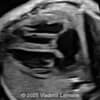

A 33-year-old nullipara with non-contributory medical history presented at 20 weeks, 6 days based on an early scan. Ultrasound revealed the following findings. There were no other apparent abnormalities. What is the most probable diagnosis?